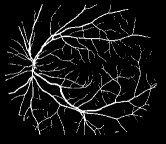

Refer to caption

Figure 1: Vessel segmentation results of side-output(s-out) layers produced by three networks. From top to bottom the network is normal DSN (with no short connections), BS-DSN (DSN with bottom-top short connections) and BTS-DSN (DSN with both bottom-top and top-bottom short connections), respectively.

As pointed out in recent works [15, 17], a good semantic segmentation network should learn multi-level features. Further, it should have multiple stages with different receptive fields to learn more inherent features from different scales. FCN, taken as an example, uses skip connections to fuse multiple stages outputs, as well as the HED network, in which a series of side-output layers are added after each stage in VGGNet. The HED network was first proposed for edge detection, and further used for image-level vessel segmentation in recent studies [6, 16], with significant performance. However, our experimental results show that such network architecture is not appropriate for vessel segmentation directly. Figure 1 provides such an illustration. Reasons for this phenomenon are straightforward. On one hand, the side-output of the first layer often contains too many noises. On the other hand, the features produced by the last side-output layer are too coarse due to information loss of pooling operation. Obviously, the inaccurate vessel map of side-output1 and side-output4 should have negative impacts on the final segmentation result.

In addition, we can observe from Figure 1 that the side-output1 and side-output4 of the BTS-DSN were more accurate compared with those of the DSN.